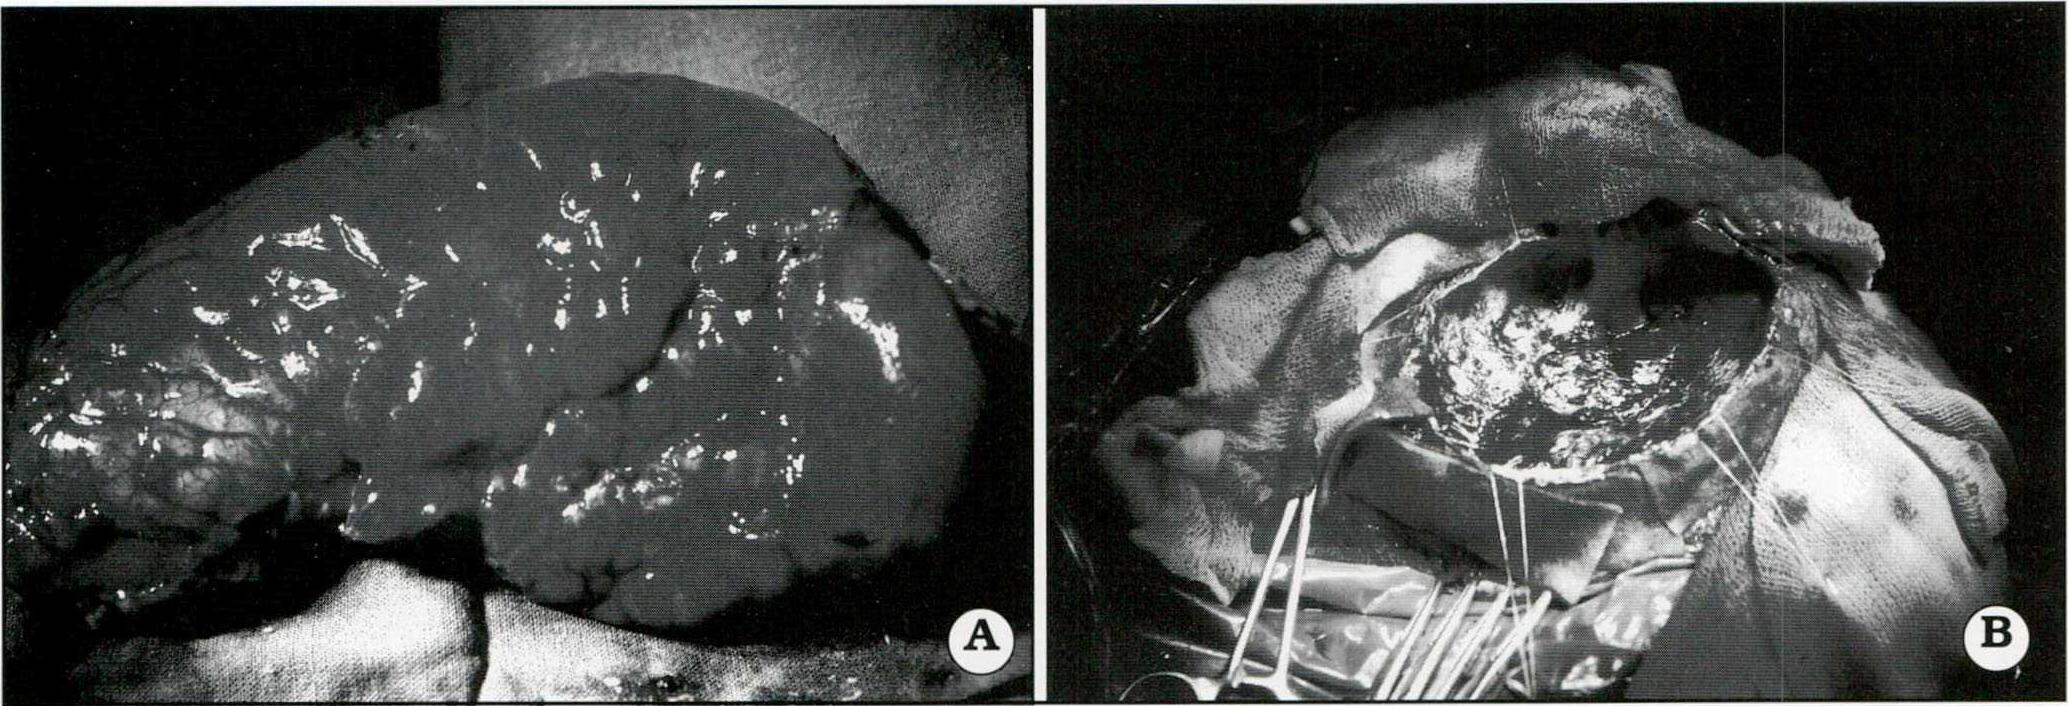

En esta serie se efectuó una única hemisferectomía anatómica en una niña de 10 meses de edad que padecía una epilepsia catastrófica secundaria a una hemimegaloencefalia (Fig. 6).

Las polectomías y/o lobectomías fueron efectuadas en 8/68 pacientes. El límite posterior de las lobectomías frontales fue el surco precentral. El lateral, 1,5 a 2 cm de la pars opercularis y triangularis del lóbulo frontal, el medial 0,5 a 1 cm de la línea media tratando de respetar la circonvolución supracallosa y la del cíngulo, siempre que no asentara en ellas el área epileptogénica primaria. El limite basal (área frontoorbitaria) lo da la sección del girus recto14. Las resecciones occipitales se efectuaron en pacientes con hemianopsias previas14. La resección del área central y lóbulo parietal efectuada en los niños de hasta 7 años de edad no agregó déficits neurológicos.

Fig. 6. A. Hemisferectomía anatómica. Pieza quirúrgica. Paciente con hemimegaloencefalia. B. Lodge quirúrgica. La IRM preoperatoria y la TAC postoperatoria pueden verse en la parte I de este trabajo. (Rey. Argent. de Neurocirugía.1999.